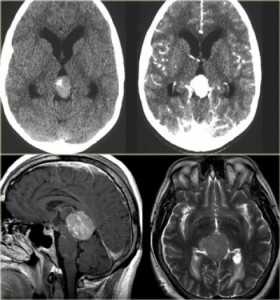

МРТ головного мозга. Сагиттальная и аксиальная Т1-взвешенные МРТ, аксиальная Т2-взвешенная МРТ и аксиальные КТ и Т1-взвешенная МРТ с контрастированием. Гигантоклеточная астроцитома с кальцификацией - внутрижелудочковая опухоль.

КТ и МРТ головного мозга. Аксиальные КТ до и после контрастировали, сагиттальная МРТ с контрастировавшем, аксиальная Т2-взвешенная МРТ головного мозга. Герминома (КТ и МРТ)- опухоль области шишковидной железы